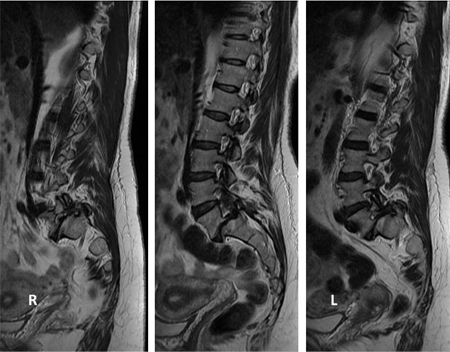

[Figure caption and citation for the preceding image starts]: Pre- and post-surgical views: a patient presents with back pain and neurogenic claudication with stenosis and degenerative slip at L4-5 and a degenerate disc at L5S1 (left, T2-weighted sagittal MRI); L4-S1 decompression and instrumented fusion and a 2-level transforaminal lumbar interbody fusion was performed (AP radiograph top; lateral, bottom)From the collection of Dr N. Quiraishi [Citation ends].